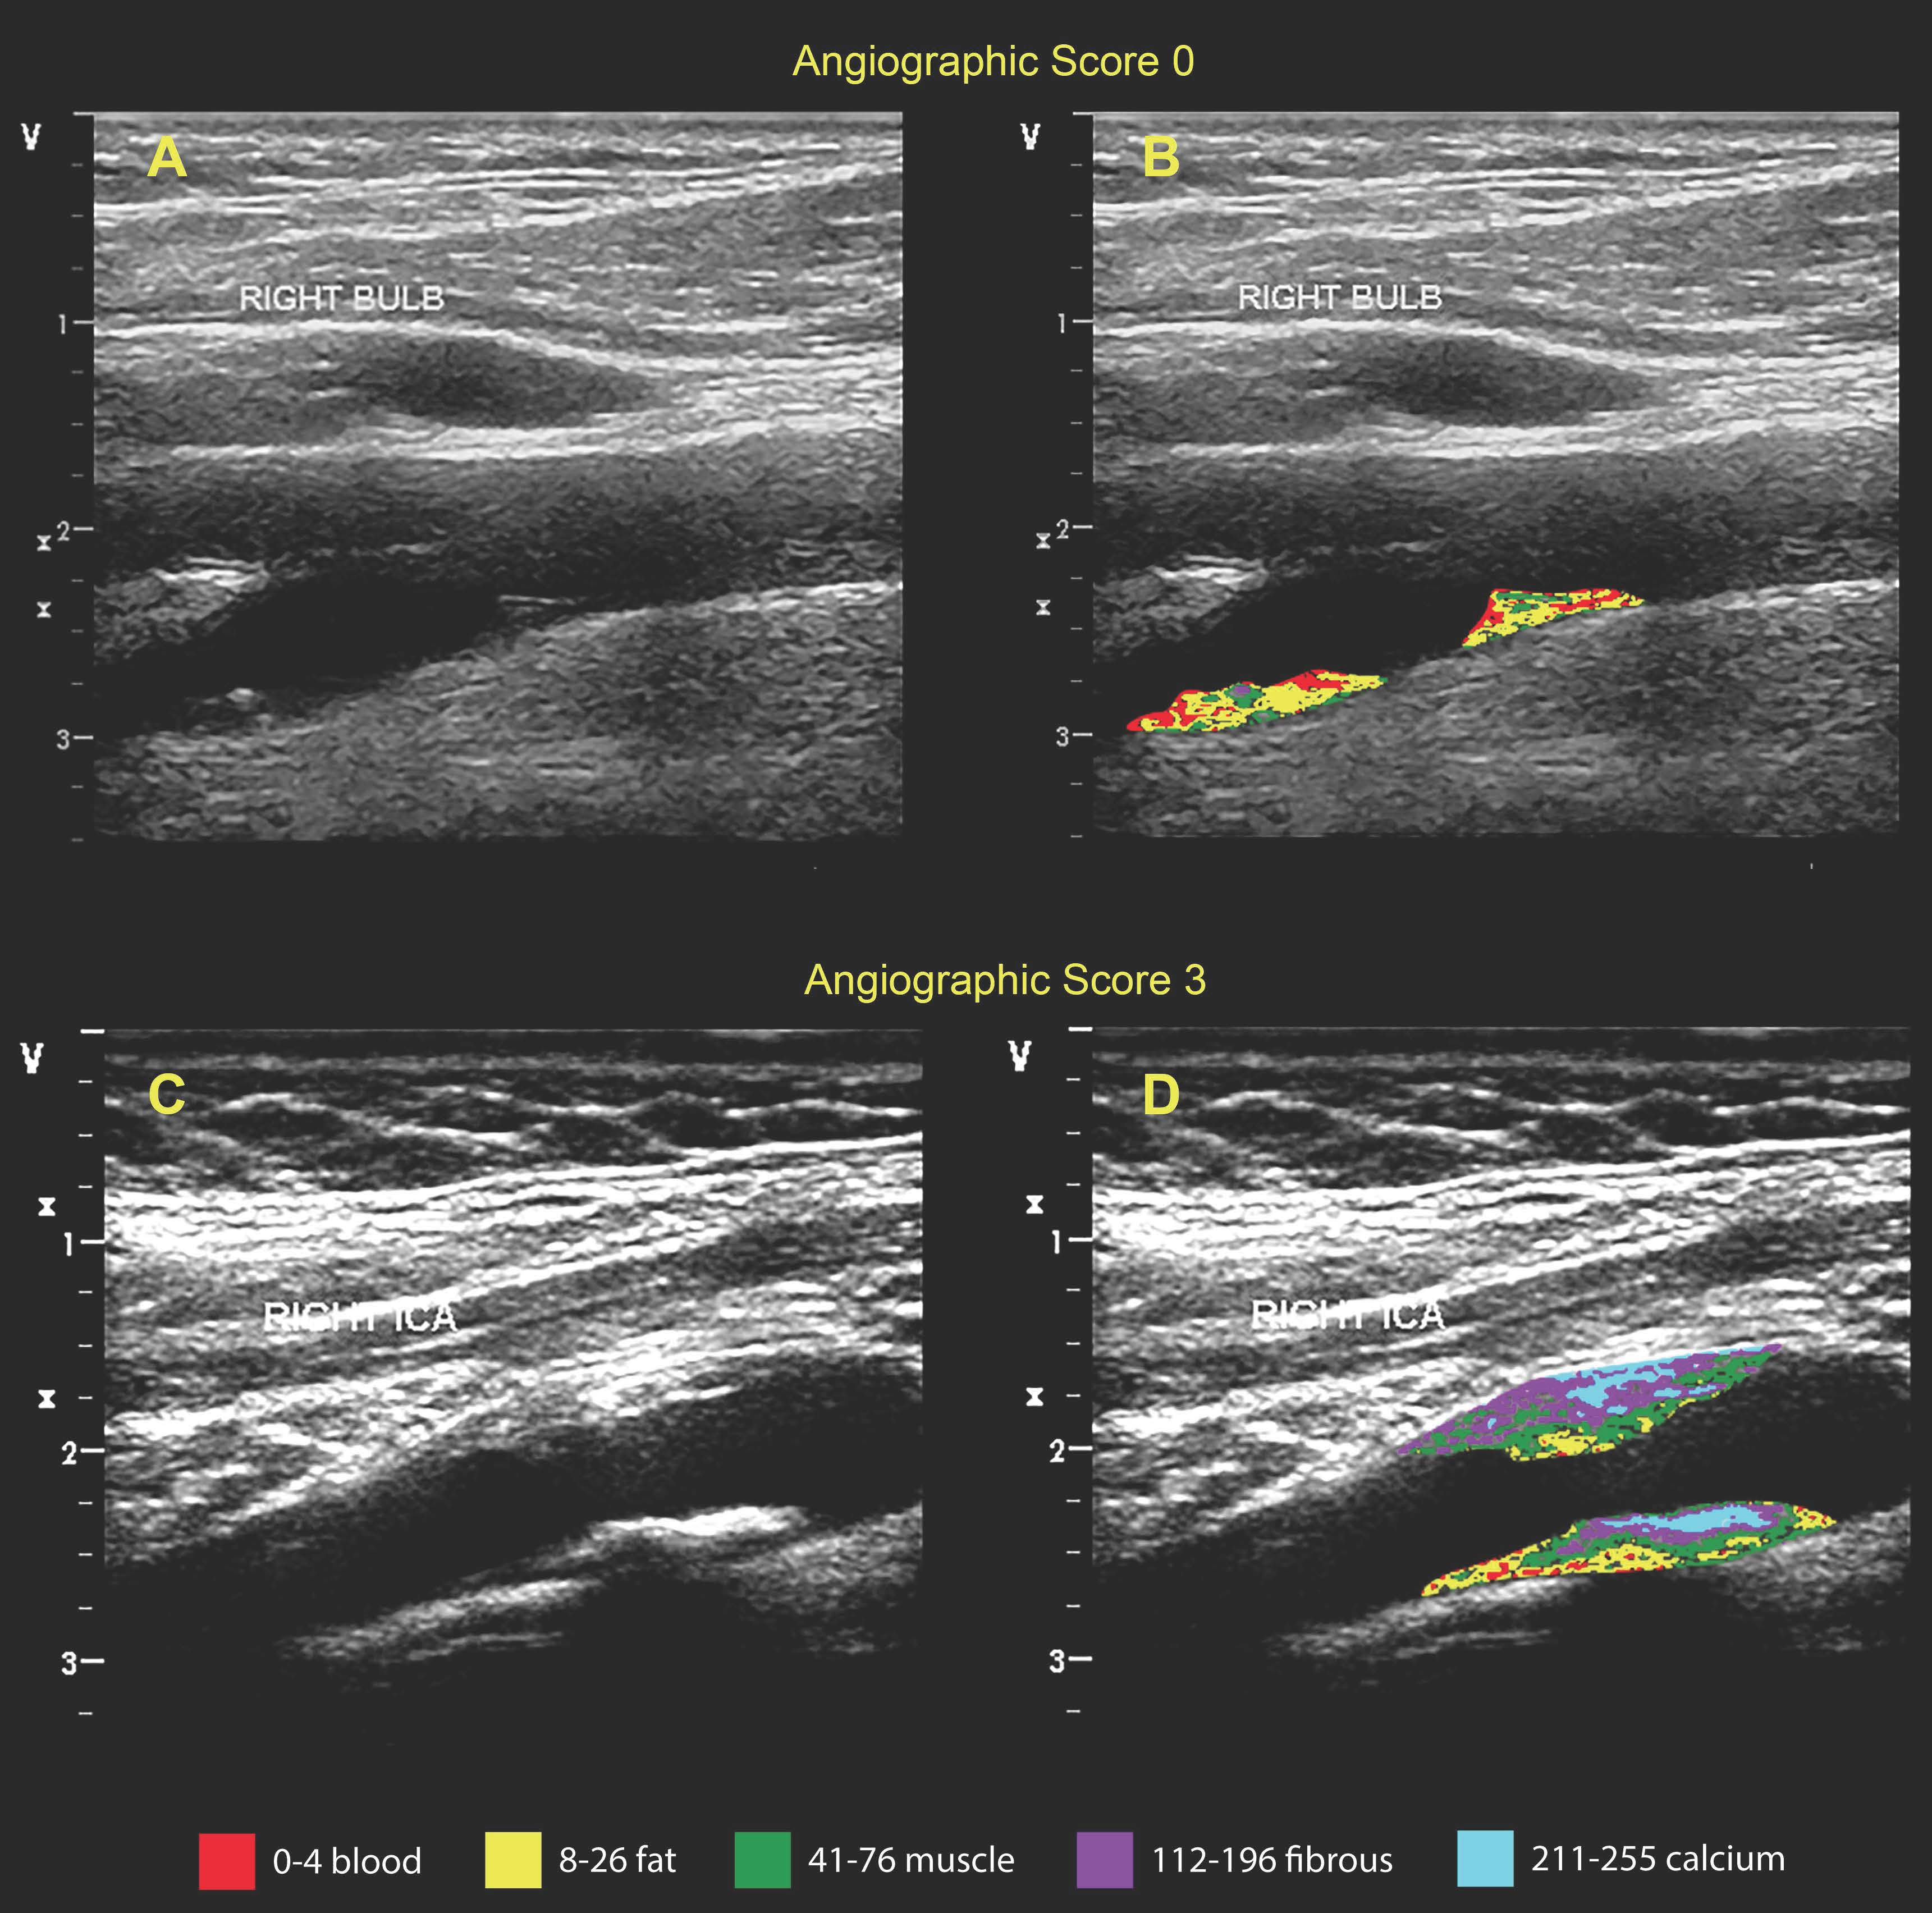

A focused carotid ultrasound was performed in 522 participants who had recently undergone coronary angiography. In 468 participants found to have atherosclerotic plaque in at least one carotid artery, plaque composition was assessed for tissue-like types: grayscale ranges 0-4 (blood), 8-26 (fat), 41-76 (muscle), 112-196 (fibrous), and 211-255 (calcium). Logistic regression was used to evaluate correlations with significant CAD (≥50% stenosis). Cox proportional hazards models were used to determine risk for 5-year CV outcomes.

Fig. 2